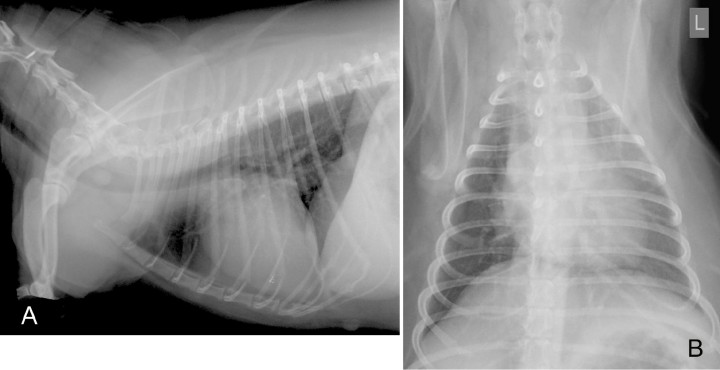

Se presenta en consulta una perra, hembra, mestiza, de 7 años y 11 kg de peso, con historia de crisis respiratorias (ahogos) de dos semanas de duración. Se había tratado a la paciente con prednisona, furosemida y benazepril, sin evidencia de mejoría. El examen físico mostraba obesidad (5/5) y leve disnea sin tos. En el análisis sanguíneo se observó neutrofilia con desviación a la izquierda (35 x103/μl; rango 3-12 x103/μl) e hiperglobulinemia (4,9 mg/dl; rango 2,6-3,8 mg/dl). Se realizaron radiografías de la cavidad torácica en proyecciones lateral derecha (Fig. 1A) y ventrodorsal (Fig. 1B).

<p>Radiografías de la cavidad torácica de una perra mestiza de 7 años. (<strong>A</strong>) Proyección lateral derecha. (<strong>B</strong>) Proyección ventrodorsal.</p>

Radiografías de la cavidad torácica de una perra mestiza de 7 años. (A) Proyección lateral derecha. (B) Proyección ventrodorsal.